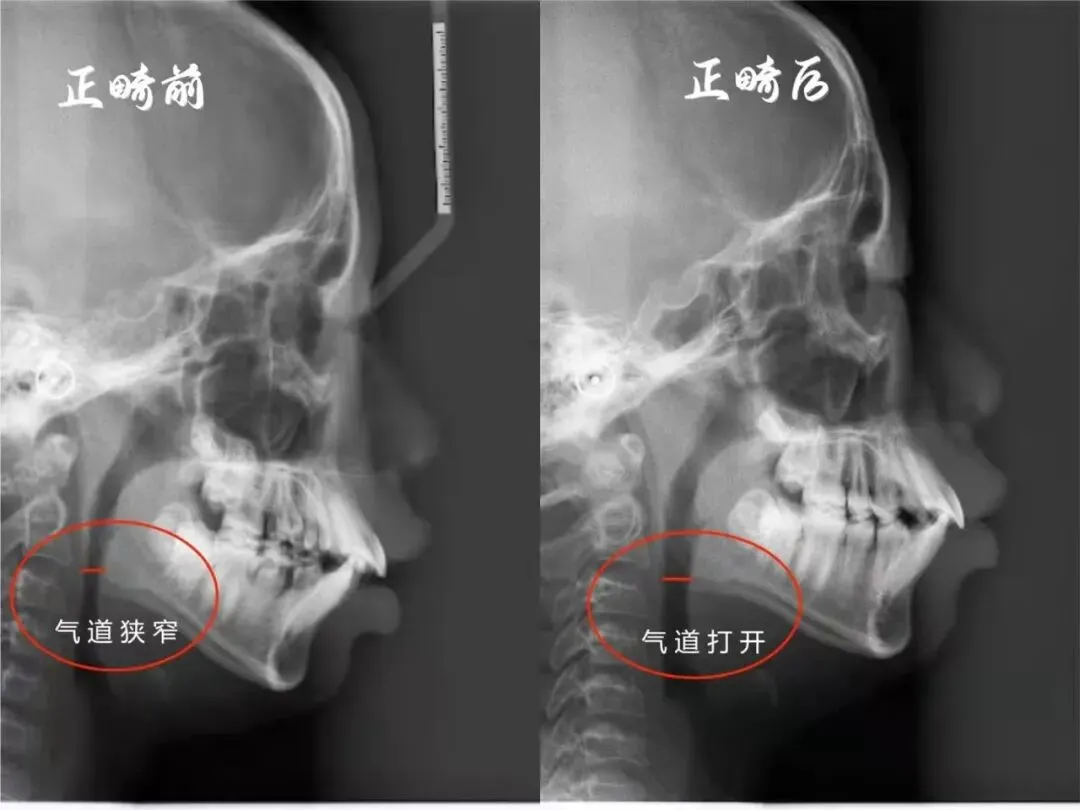

头颅侧位片表现:口呼吸孩子的头颅侧位片中部分气道比正常鼻呼吸儿童明显减少,鼻咽部轻微阻塞就易使气道变狭窄而发生口呼吸。